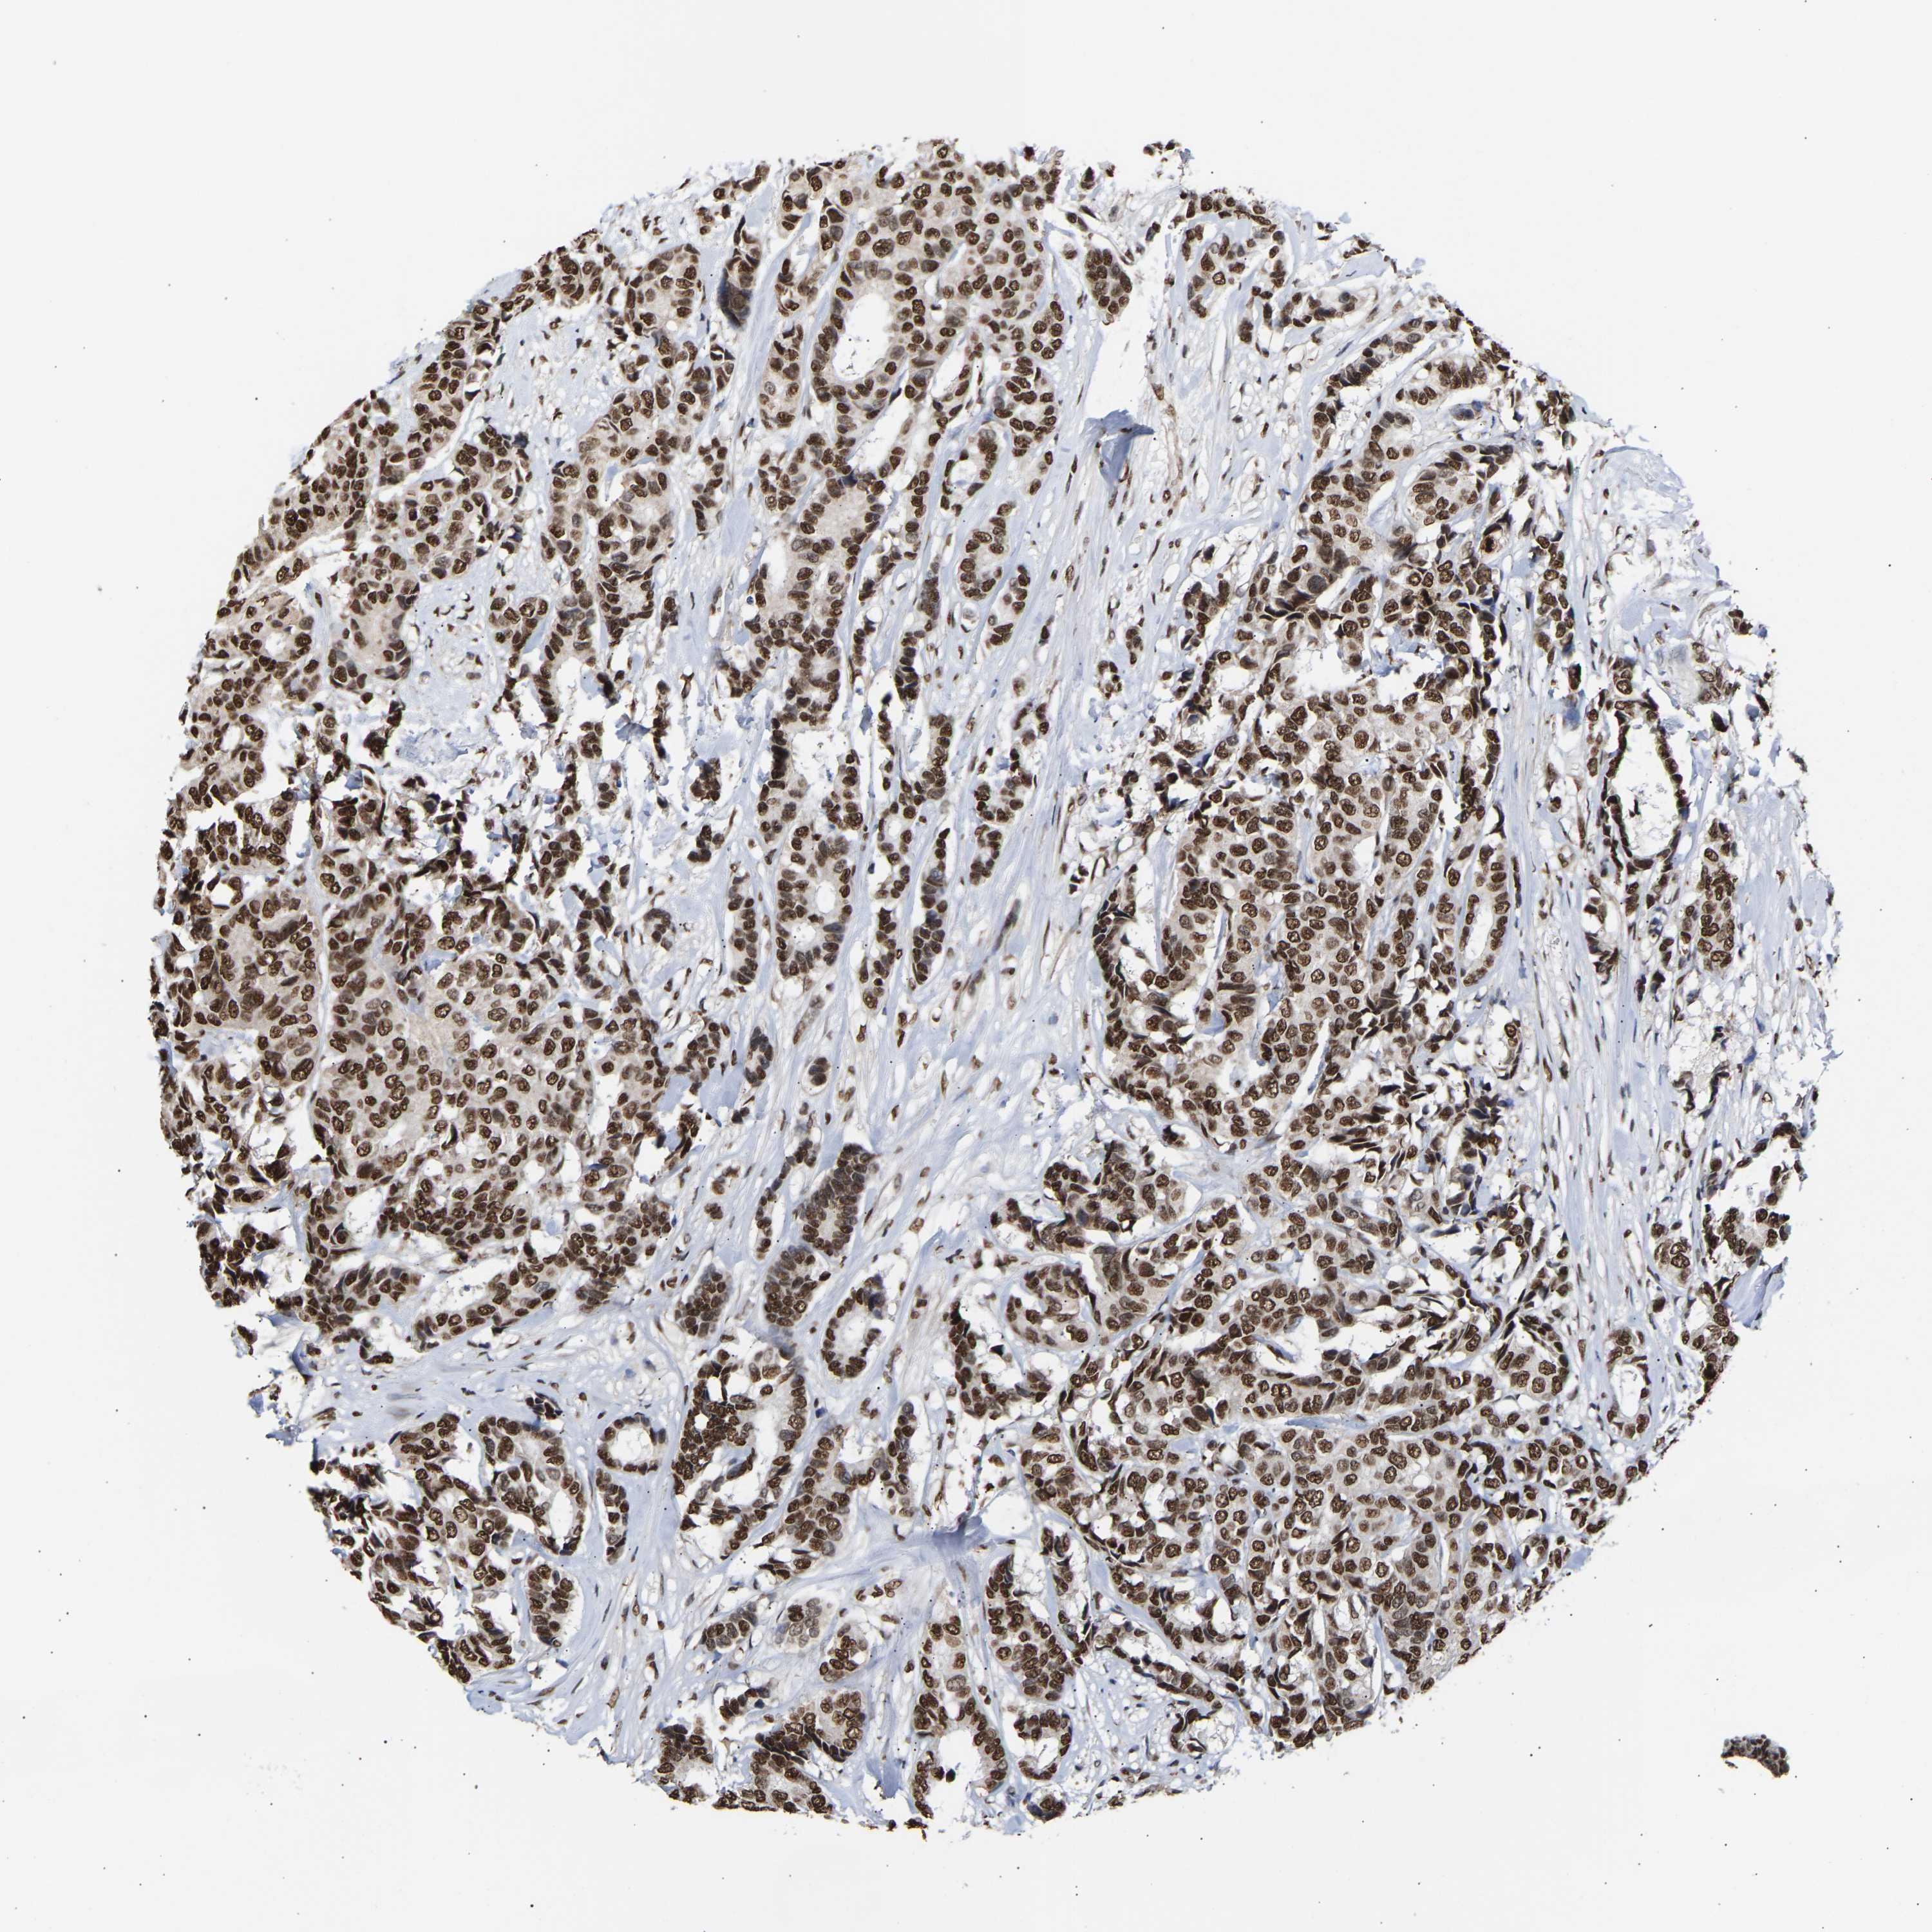

CANCER BREAST CANCER Show tissue menu

BRCA TCGA BRCA VALIDATION PROTEIN EXPRESSION